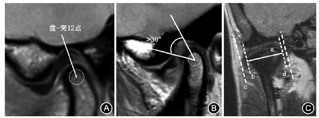

①按移位层面分为正常上位(关节盘后带后缘位于髁突上方12点的位置,即"盘-突12点")(图2A)、部分移位(部分层面移位)、完全移位(所有层面均移位)[3,9];②按移位方向分为前移位、后移位、内侧移位及外侧移位,关节盘后带后缘的切线与经过髁突12点方向的垂线前后夹角超过10°为前移位(图2B),关节盘内缘或外缘超过经髁突内外极连线长轴的垂线为侧方移位(图2C);③按前移位程度分为正常上位(0~10°)、轻微前移位(11~30°)、轻度前移位(31~50°)、中度前移位(51~80°)、重度移位(>80°)[10,11];④按张口位关节盘是否恢复正常位置分为可复性移位或不可复性移位。